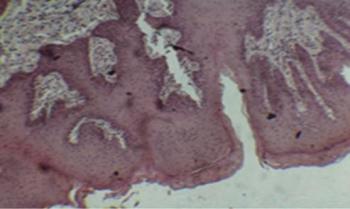

Az alábbiakban részletesen tárgyalandó számos daganatmegelőző elváltozás részben környezeti hatásra, részben szisztémás betegségek részjelenségeként kialakuló kóros állapot, amely a karcinogén behatásokra feltehetően fokozottabban érzékeny. Az ezeken a területeken megfigyelhető rendellenes hámképzésre jellemző példa a leggyakoribb szájüregi praecancerosis – a leukoplakia – szövettani képében megfigyelhető hyperkeratosis, parakeratosis, hámhyperplasia, különböző súlyosságú dysplasia, melyekhez a hám alatti kötőszövet idült gyulladása csatlakozhat (10.1. ábra).

10.1. ábra. Leukoplakia szövettani képe